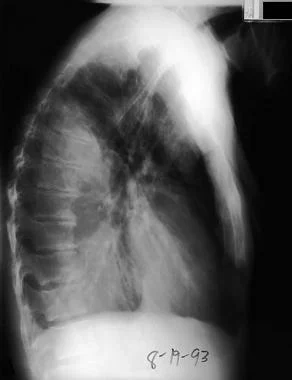

图2 侧位胸片显示,左侧有较多积液。